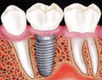

• 앞니 임플란트? 임플란트 틀니?